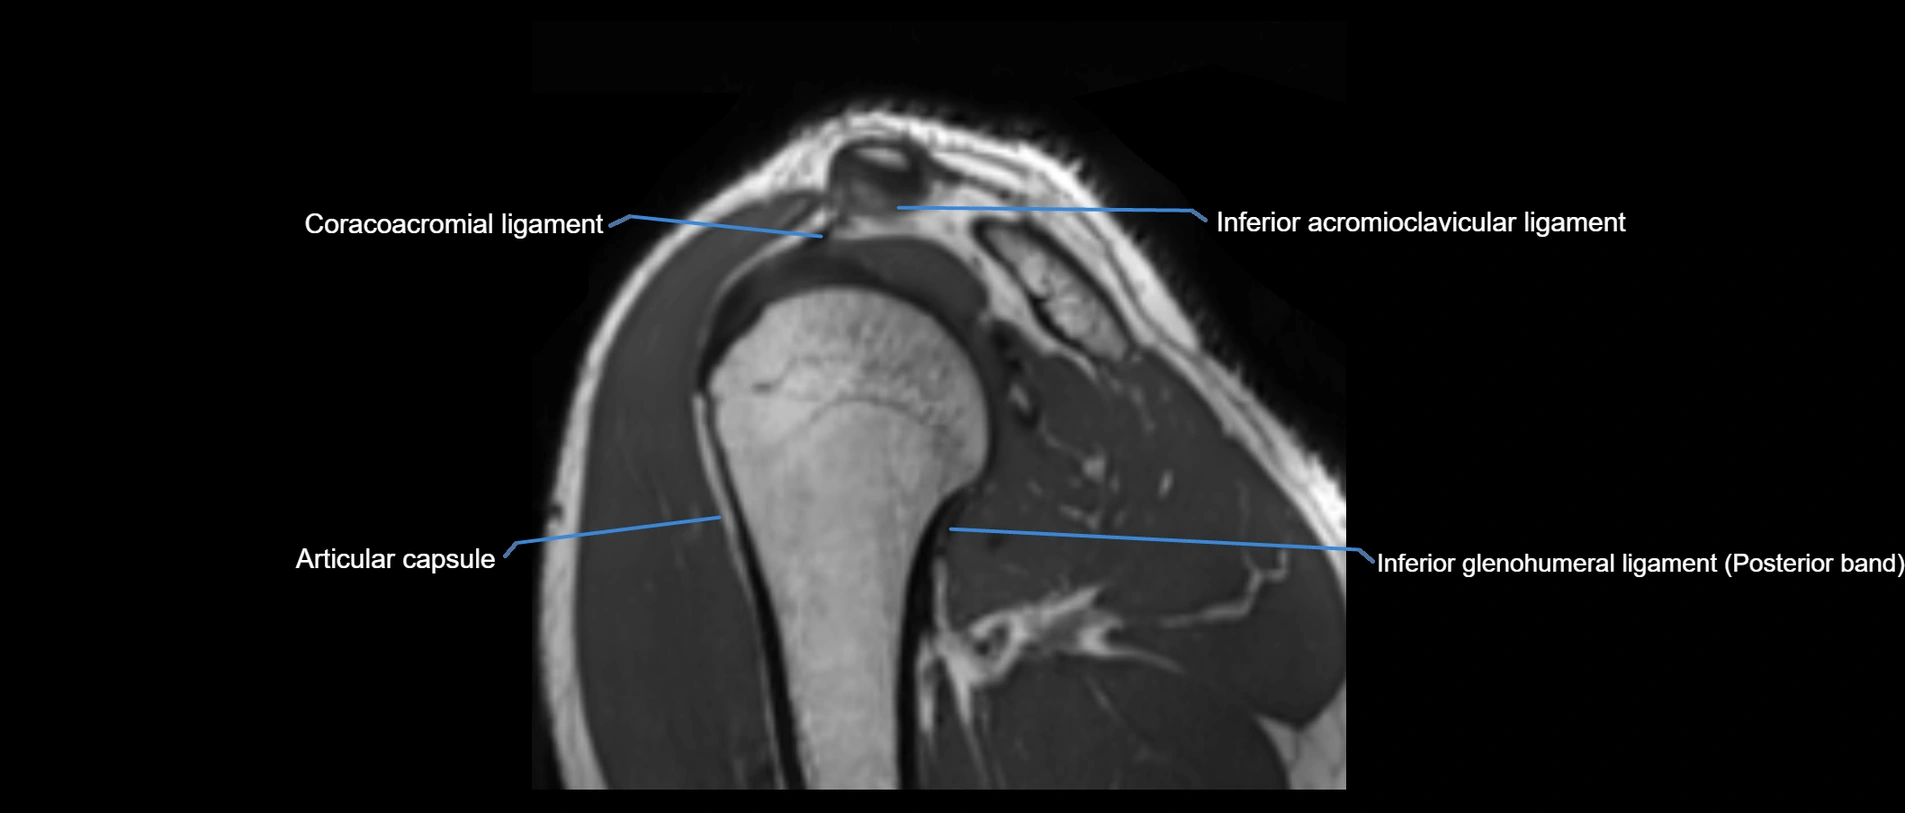

MRI Appearance

• T1-weighted images:

• Normal ligament: Low signal (dark linear band) spanning acromion to clavicle.

• Surrounding fat planes: Bright, delineating the ligament clearly.

• Marrow of clavicle and acromion: Bright due to fatty content.

• Tears: Discontinuity or irregular thickening with intermediate-to-bright signal.

• Chronic injury: Thinning, fraying, or irregular low-signal fibers with adjacent scarring.

• T2-weighted images:

• Normal ligament: Low signal, homogeneous.

• Partial tear or sprain: Focal hyperintensity or thickening.

• Complete tear: Discontinuity with fluid-bright gap between clavicle and acromion.

• Associated edema: Bright signal in distal clavicle or acromion marrow.

MRI images

image